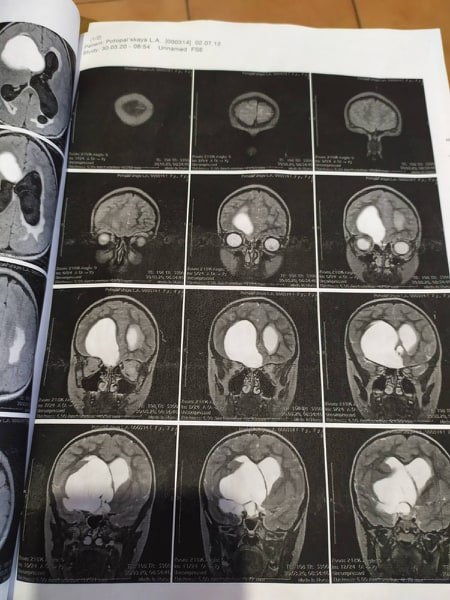

Юна кременчужанка Лілія Потопальська на боротьбу з пухлиною мозку потребує близько 100 тисяч гривень. У дівчинки виявили кістозну гігантську краніофарингіому з ознаками прогресуючої оклюзійної гідроцефалії. Як говорять кошти необхідні на вчора, адже лікування дороговартісне, а коштів у родини вже обмаль.

Подруга родини Юлія поділилася з «Телеграфом», що дівчинка навчається у школі й любить дізнаватися щось нове. Останнім часом у Лілі різко почав втрачатися зір та пам’ять. Після медичних оглядів виявили пухлину з розміром у тенісний м’ячик.